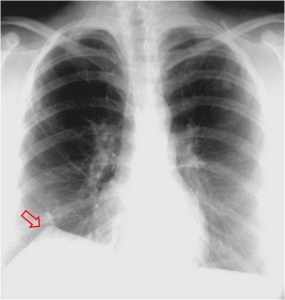

SIGNO DE LA ALTERACIÓN DEL CONTORNO AÓRTICO

La irregularidad, abombamiento o borramiento del arco aórtico en la radiografía de tórax en bipedestación o en decúbito supino, en un paciente con traumatismo torácico, obliga a descartar rotura aórtica como causa de dicha alteración. La flecha muestra el contorno aórtico anómalo. Además, hay un aumento de densidad en el hemitórax izquierdo correspondiente a derrame pleural –hemotórax en este caso-, que refuerza la sospecha de rotura aórtica.